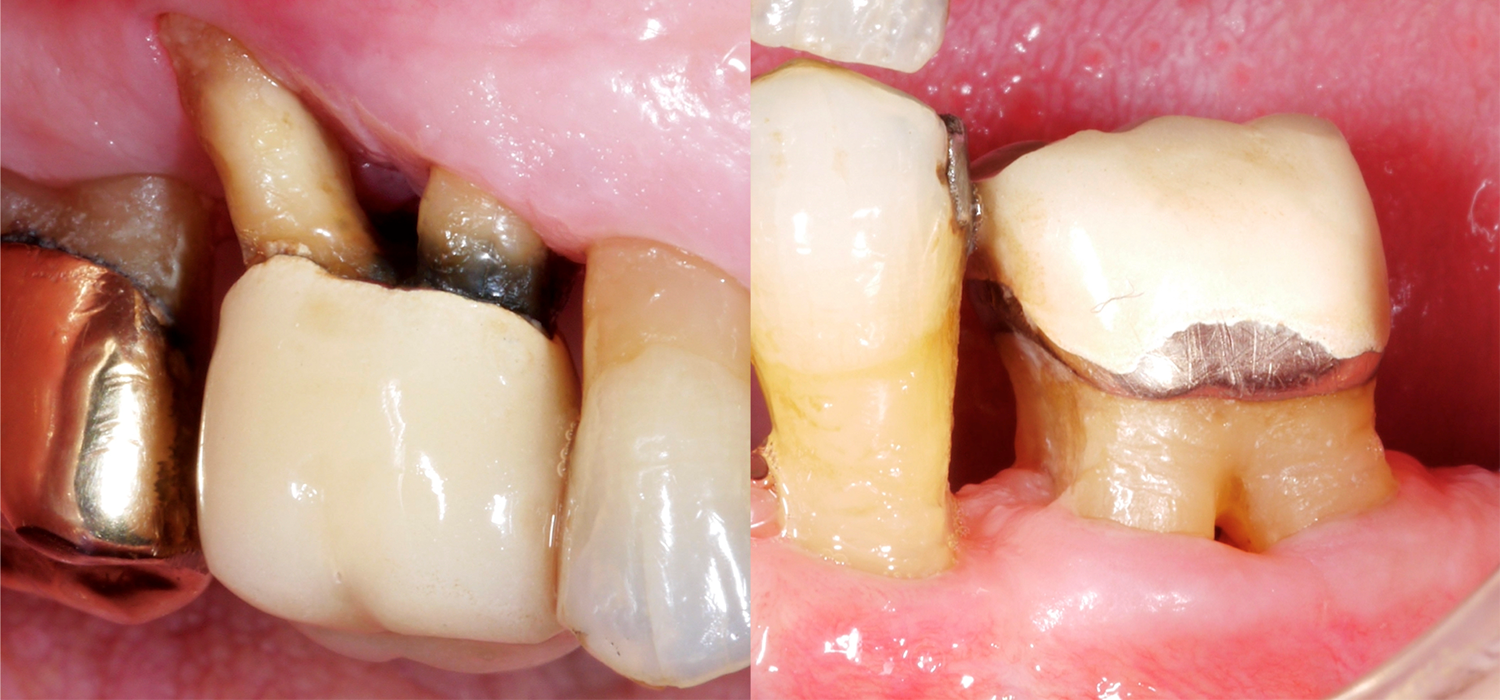

Если речь идет о многокоренных зубах , то, как правило, их лечение значительно сложнее, особенно если они имеют дефекты в области фуркаций. Почему область фуркаций представляет собой такую сложность? По сравнению с однокорневыми зубами доступ для механической очистки поверхности корня значительно затруднен, вход в фуркацию часто может быть очень маленьким/узким, а также могут присутствовать дополнительные анатомические особенности, например, выступы эмали.

Так, в систематическом исследовании 2016 г. (Nibali et al.) было показано, что зубы с дефектом фуркации примерно в два раза чаще удаляются после 10-15 лет поддерживающего пародонтологического лечения. Риск потери зуба также возрастает тем больше, чем выше класс дефекта фуркации; так, вероятность потери моляра со сквозным дефектом фуркации (класс III) примерно в три раза выше, чем моляра с дефектом фуркации класса I.

В недавно опубликованном исследовании из Франкфурта (Eickholz 2021) рассматривались именно зубы со сквозным дефектом фуркации. Всего было изучено 265 зубов со сквозным дефектом фуркации у 160 пациентов; все пациенты получали поддерживающее пародонтологическое лечение не менее пяти лет. Исходя из этих данных, мы должны принять во внимание следующие важные моменты:

• Зубы с III степенью фуркации теряются чаще, чем, например, однокорневые зубы, также мы должны учитывать, что примерно через 10 лет поддерживающей пародонтологической терапии около трети этих зубов были удалены. Однако, в то же время это также означает, что две трети этих зубов, подвергшихся серьезному пародонтальному повреждению, удалось сохранить!

• Причины удаления зуба могут быть самыми разнообразными - от пародонтологических проблем до кариеса и/или проблем с протезированием.

• Для зубов со сквозным дефектом борозды были выявлены следующие факторы риска потери: более высокий уровень потери костной ткани на начало лечения и более высокая глубина зондирования на начало поддерживающей терапии.